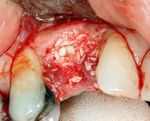

An incision is made across the area and the flap of gingiva is opened to show the bone of the jaw.

An incision is made across the gingiva, and the flap of tissue is reflected to show the bone of the jaw.

If bone width is inadequate it can be regrown using either artificial or cadevaric bone pieces to act as a scaffold for natural bone to grow around.